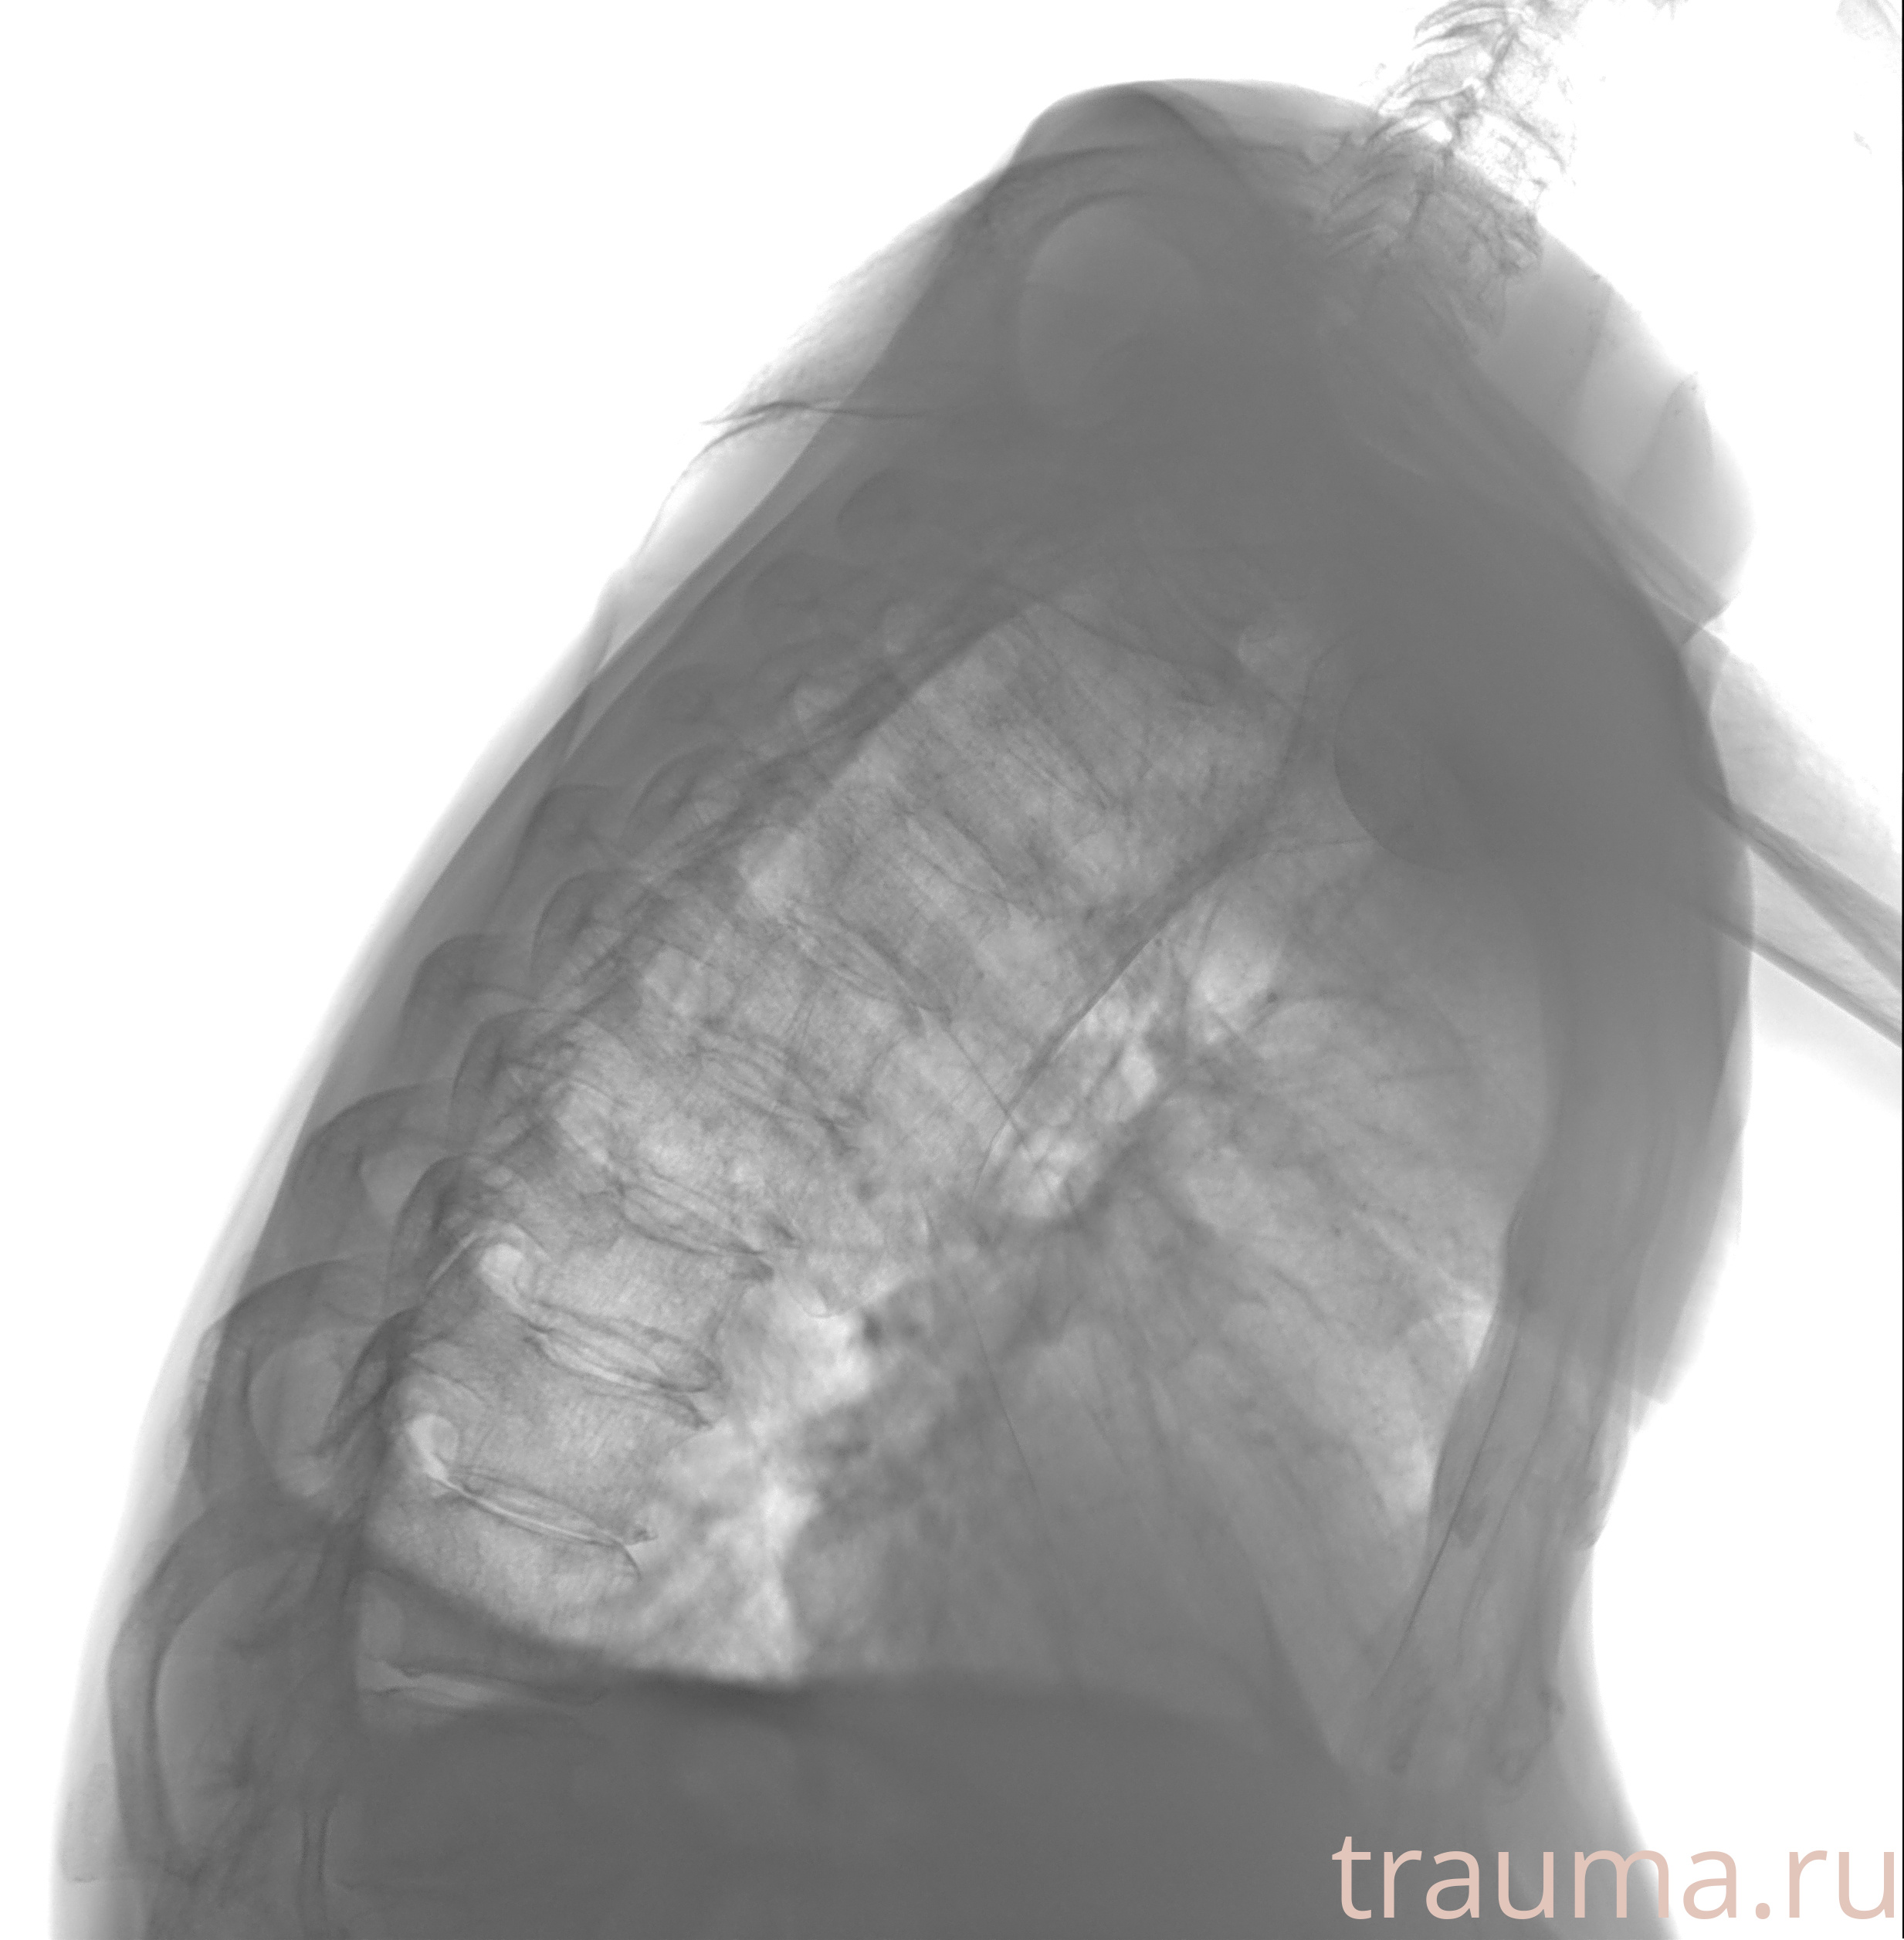

Рентгенограммы

Натуживание 26.12.2025 21:16:34

Рентген на дому: по вашему адресу приезжает врач-рентгенолог, травматолог-ортопед с мобильным рентгеновским аппаратом, проводит диагностику травмы или заболевания, делает необходимые рентгенограммы, дает рекомендации по дальнейшему лечению. Получить качественные снимки в домашних условиях возможно благодаря уникальной методике, разработанной МосРентген Центром для института  Склифосовского